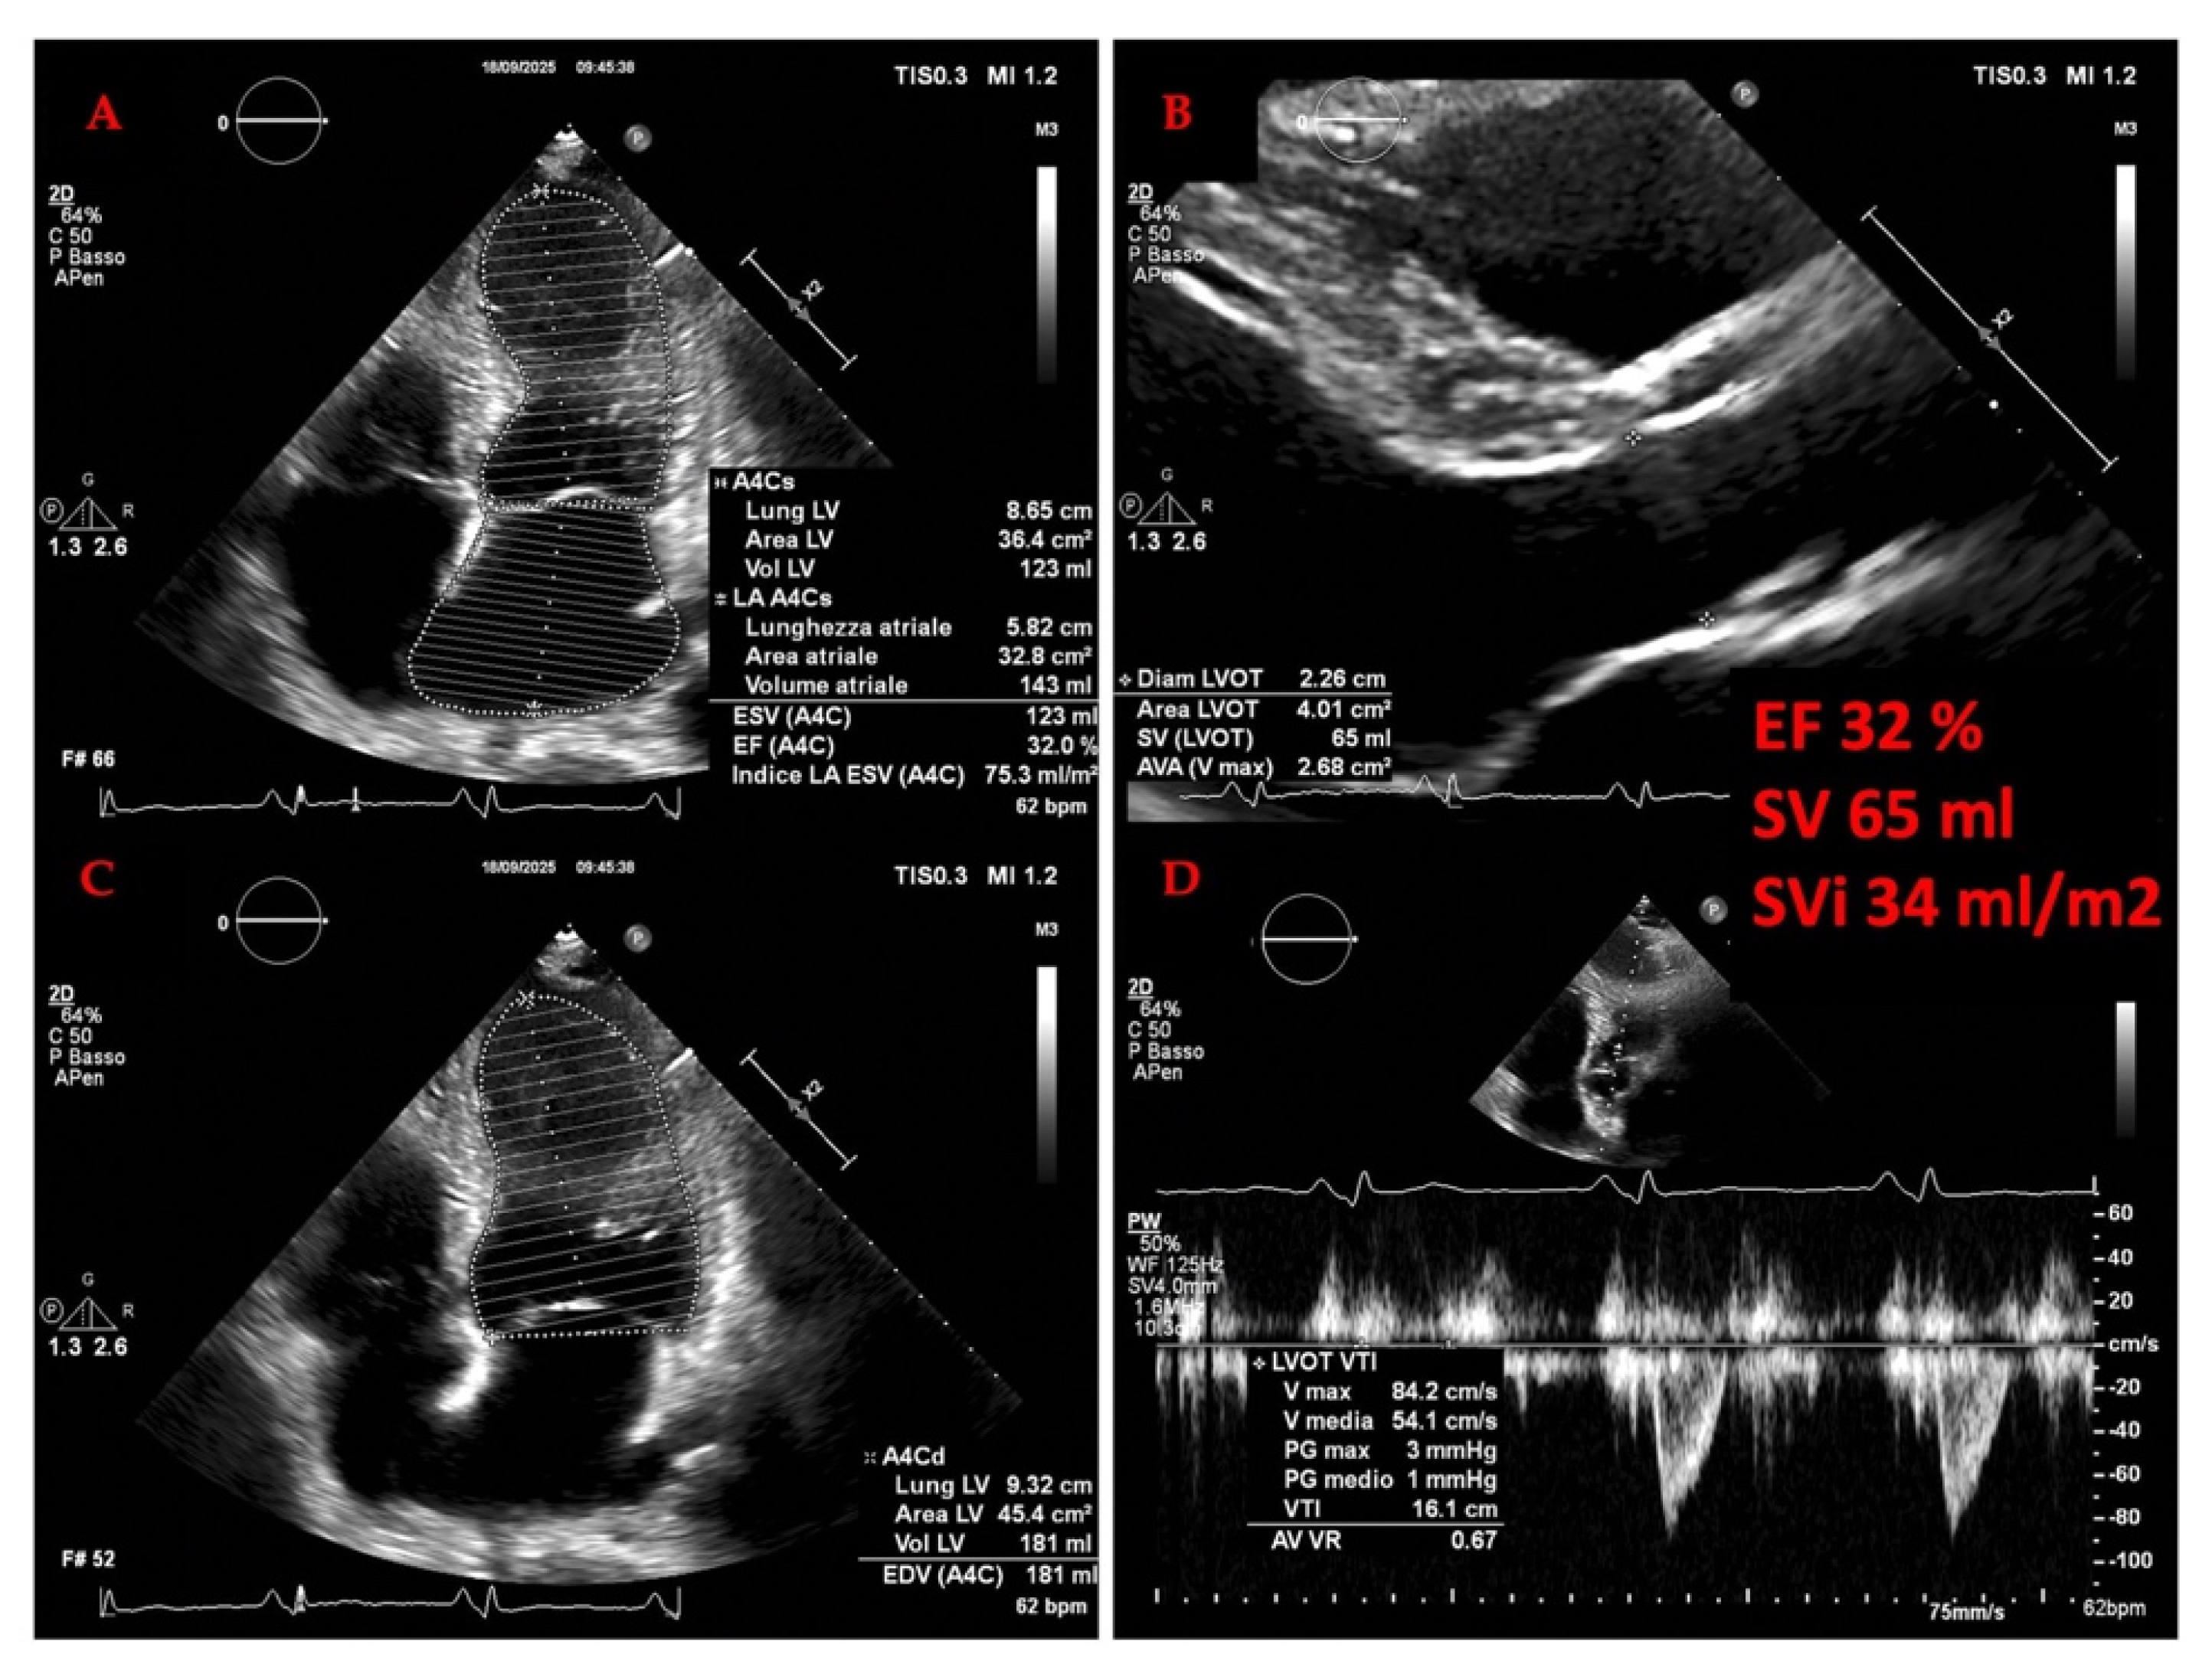

3.2.1. The Evolving Role of Echocardiography of Left Heart in Heart Failure

3.2.3. Echocardiography in Advanced Heart Failure